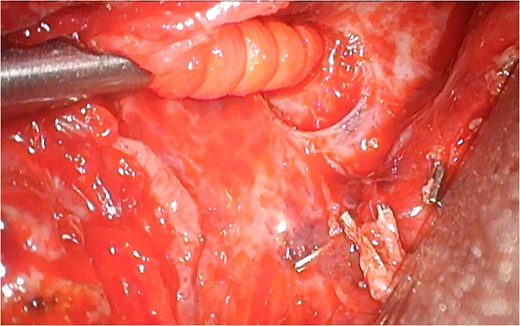

Enteral feeding with low-fat elemental formula was commenced in the morning on postoperative Day (POD) 1; however, hemodynamic instability suddenly developed in the afternoon on the same day. Echocardiography performed during cardiopulmonary resuscitation demonstrated massive pericardial effusion. Emergency ultrasound-guided drainage was performed via the subxyphoid approach; 350 mL of serous fluid was drained, and the patient’s hemodynamic status dramatically improved. After changing to fat-containing polymeric formula on POD 5, a small amount of chylous fluid was contained in the pericardial drainage fluid, but not in the bilateral pleural drainage fluid. Because the chylous fluid disappeared immediately after returning to the elemental formula, the right pleural, pericardial, and left pleural drains were removed sequentially. A fat-reduced diet was given to the patient; however, the cardiac tamponade relapsed and the pericardial drain was re-inserted on POD 13. A computed tomography scan demonstrated the presence of a retrocardiac fluid collection, encompassed by the left pulmonary vein and left atrium, descending aorta and vertebral column (Fig. 1). The initial pericardial drainage fluid was serous, but it changed to chylous again after a challenge with polymeric formula. Under the diagnosis of chylopericardial tamponade communicating with a posterior mediastinal chylocele, surgical exploration was performed via the left-sided thoracoscopic approach on POD 20. A chyle leak from a tributary of the thoracic duct was easily recognized because of the administration of polymeric formula immediately before surgery. The leak was stopped with surgical clips. A pericardial hole, which had been made during the esophagectomy, was confirmed to be close to the leakage point (Fig. 2). The hole was left open and a closed suction drain was placed in the posterior mediastinum.

A pericardial hole was confirmed to be close to the leakage point.